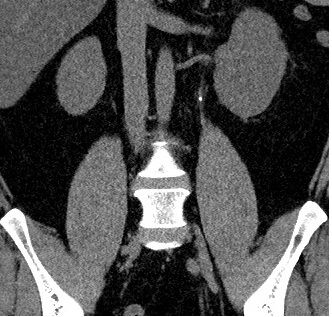

집앞 내과 방문후 ct찍고 요로결석 판정을 받고나서 ct 자료 들고 강동성심병원에 연계되어 갔습니다

2주후 강동성심병원에서 ct, 소변검사 진행했으며 소변검사 이상없음 ct에선 결석위치 변동없음

혈뇨나 통증은 없으며 무조건 수술해야된다 크기 물어보니 4mm 이며 자연배출 하겠다고 하고 한달 약처방받앗습니다